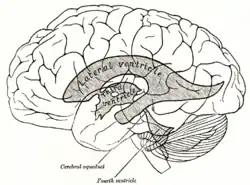

Transverse dissection showing the ventricles of the brain.

Transverse dissection showing the ventricles of the brain. 3D Model of ventricular system